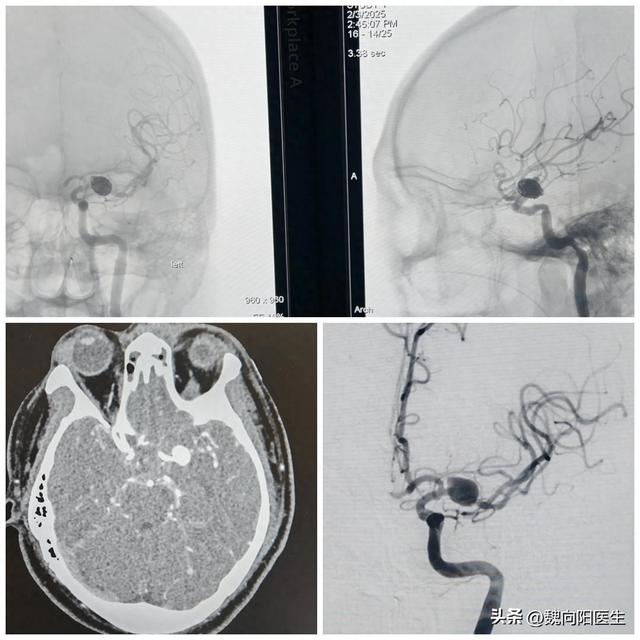

脑动脉瘤手术后的后遗症(都是动脉瘤破裂引起的脑出血)

今天连续收治了两例动脉瘤破裂导致的脑出血患者,但是治疗结果却截然不同。第一例脑出血患者45岁,男性。该患者下床时,突发的头晕伴有头痛晕倒在地,休息之后,头痛症状却越来越严重,且出现恶心呕吐症状,特来医院行头ct:“蛛...